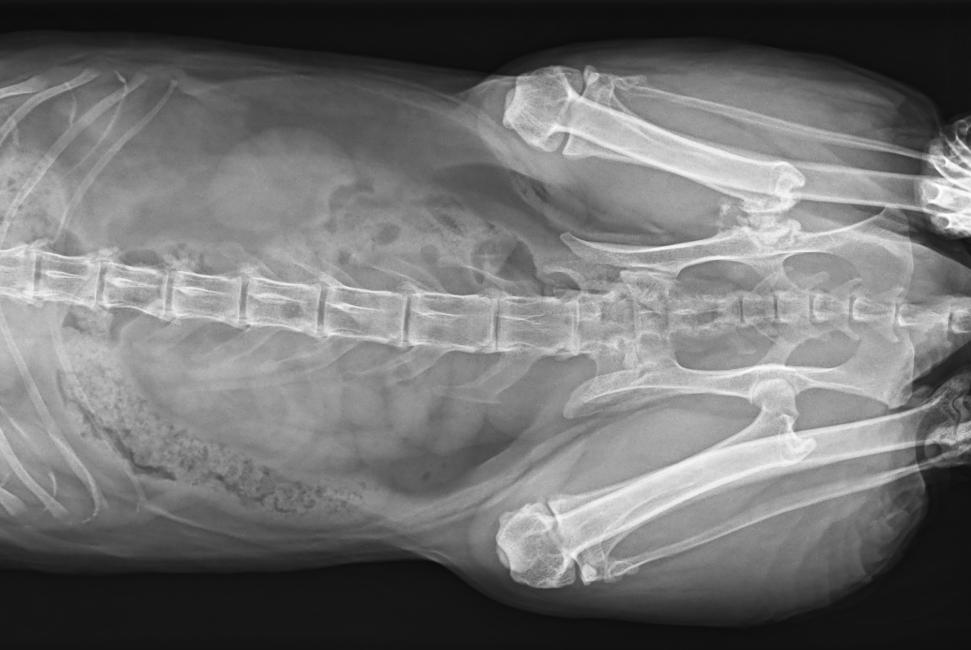

● 可浮動床面設(shè)計,滿足大部分中小型寵物檢查

● 靈巧機架設(shè)計,近臺操作,手動/遙控曝光,結(jié)構(gòu)靈活緊湊